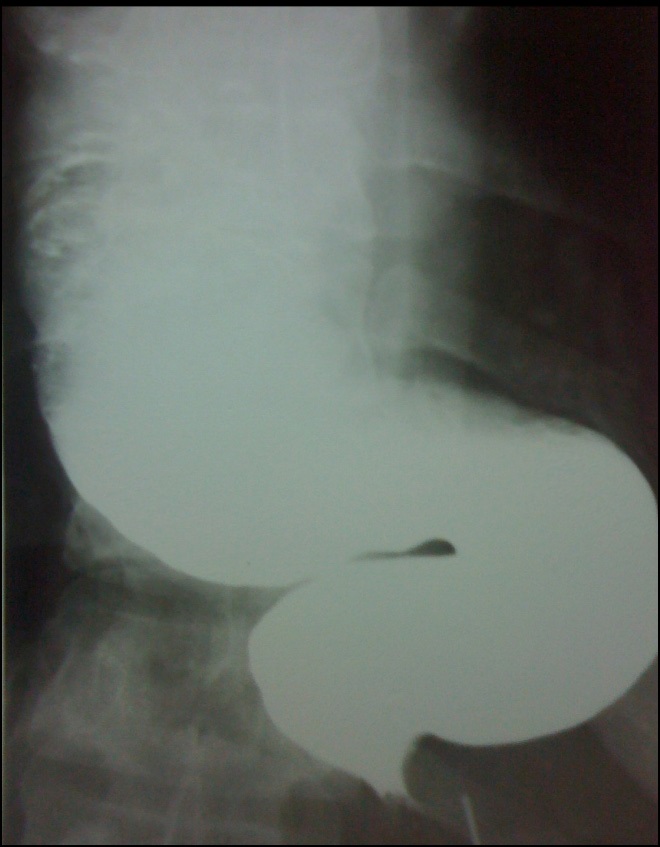

In the period between March 2008 and December 2021, 7 patients were treated minimally invasively for presenting mega esophagus due to achalasia at the end of stage (Figure 1).

Of the total, 3 corresponded to the male sex and 4 to the female sex. The average age was 54.7 with a range of 35 to 66 years. One case corresponded to a megaesophagus of Chagasic origin, and the other 6 cases were due to recurrence of the Heller-Dor myotomy, which was treated with endoscopic dilations. The treatments performed were: 1 laparoscopic transhiatal esophagectomy and a minimally invasive esophagectomy in the prone position (Figure 2) 4 esophagus ardioplasty procedures, as described in Figure 3, and 1 case of resection of the esophagogastric junction and Roux-en-Y bypass.

Figure 1: Esophagus barium swallow.